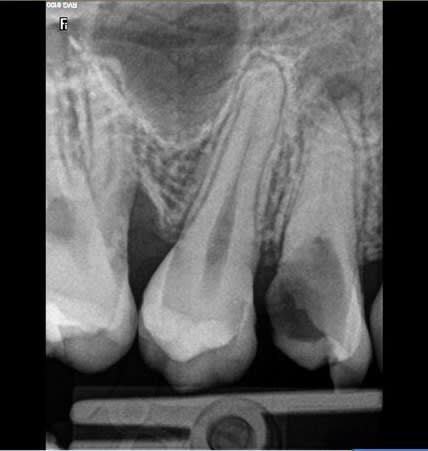

or je vous laisse voir la belle 14 , et même la 24 que je découvre

je pense de toutes façons faire l 'endo de 14 et couronner les deux, mais le pronstic n est pas terrible.. non?

Bon sa 14, elle est foutue évidemment. Sa 24 aussi à moyen terme.

J'ai une idée pour ton cas, peut-être casse-gueule ou pas, mais le cas ne l'est-il pas déjà :

1° Vérifiez l'occlusion antagoniste de 14 : que 44 et 45 soient calées sinon mise en place d'un fil collé de 43 à 46.

2° Endo de 14.

3° IC avec de la marge en occlusal pour l'étanchéité de 2°.

4° Provisoire en sous-occlusion en gardant bien les contacts proximaux.

5° Visite tous les 4/6 mois pour meuler la provisoire.

6° Élongation coronaire si l'os a suivi.

6° bis modelage gingival si pas d'alignement du collet.

On couronne, enlève le fil et c'est fini. Pour les autres dents sur pano je ne vois pas assez bien avec les aperçus d'image Eugénol.